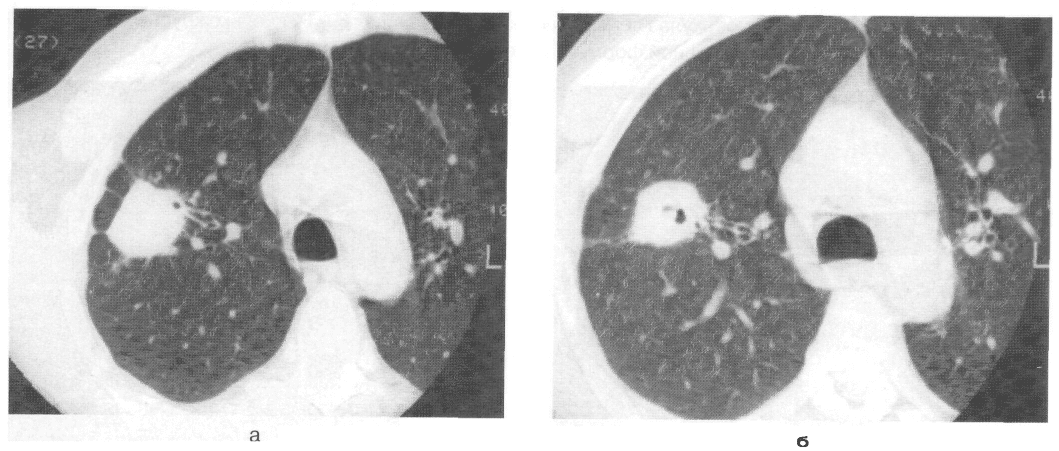

Иллюстрации по теме очагового и инфильтративного туберкулеза